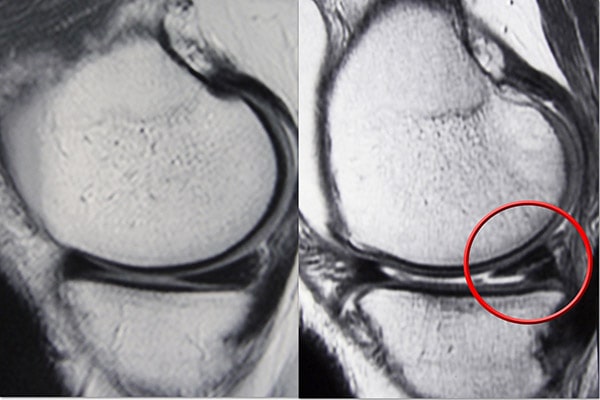

磁共振成像 (MRI) 掃描。  MRI 掃描可評估膝關節的軟組織,包括半月板、軟骨、肌腱和韌帶。

MRI 掃描顯示(左)正常的半月板和(右)撕裂的半月板。撕裂可以看作是穿過半月板黑色主體的白線